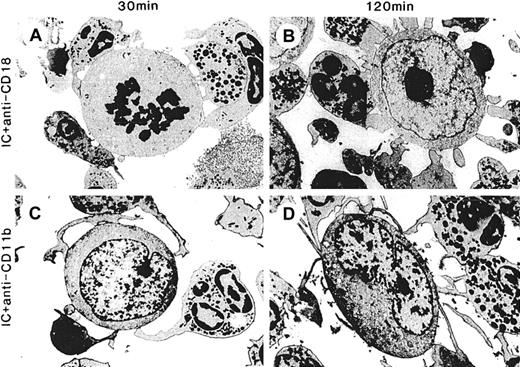

Effect of function-blocking mAbs against Mac-1 (CD11b/CD18) on spreading, adhesion, and cytolysis by PMN with hu14.18/GM-CSF.

ADCC with hu14.18/GM-CSF was as described in Figure 3 except that function-blocking mAbs were added just before the addition of hu14.18/GM-CSF. ADCC was performed in the presence of anti-CD18 7E4mAb (10 μg/mL) for (A) 30 minutes and (B) 120 minutes or anti-CD11b 2LPM19C mAb (10 μg/mL) for (C) 30 minutes and (D) 120 minutes. Electron micrographs were taken with an original magnification of × 5400.

Spreading and adhesion by PMN on target cells and cytolysis is greatest with hu14.18/GM-CSF and requires Mac-1

Cell-cell interactions between PMNs and tumor cells in ADCC were visualized with electron microscopy at 30 minutes and 2 hours after the start of ADCC. There was no or minimal spontaneous interaction between PMN and neuroblastoma cells in the absence of hu14.18 and hu14.18/GM-CSF (Figure 3A-B). In the presence of hu14.18 (Figure 3C-D) and hu14.18/GM-CSF (Figure 3E-F), PMN pseudopodia adhered to the surfaces of neuroblastoma cells. However, spreading and tight adhesion was evident with hu14.18/GM-CSF but not with hu14.18. In nearly all conjugates formed at 30 and 120 minutes with hu14.18/GM-CSF, PMNs covered 30% or more of the target cell surface, whereas in those formed with hu14.18, PMNs did not do so (Table 1). At 2 hours, most neuroblastoma cells in conjugates with hu14.18/GM-CSF were destroyed (Figure 3F), whereas those with hu14.18 remained intact (Figure 3D). Other electron micrographs of ADCC with hu14.18/GM-CSF revealed focal and global lysis of target cell membranes, spreading, and adhesion of PMN onto nuclear membranes, lysis of nuclear membranes, and phagocytosis of nuclei (data not shown). Treatment with anti-CD18 7E4 and anti-CD11b 2LPM19C blocking mAbs allowed tethering of PMN to neuroblastoma cells with hu14.18/GM-CSF at 30 minutes and 2 hours, but it completely prevented spreading, adhesion, and cytolysis (Figure4, Table 1). Tethering was mediated by Fc-FcγR interaction because all contacts were prevented when anti-FcγRII blocking Fab IV.3 was added (data not shown).